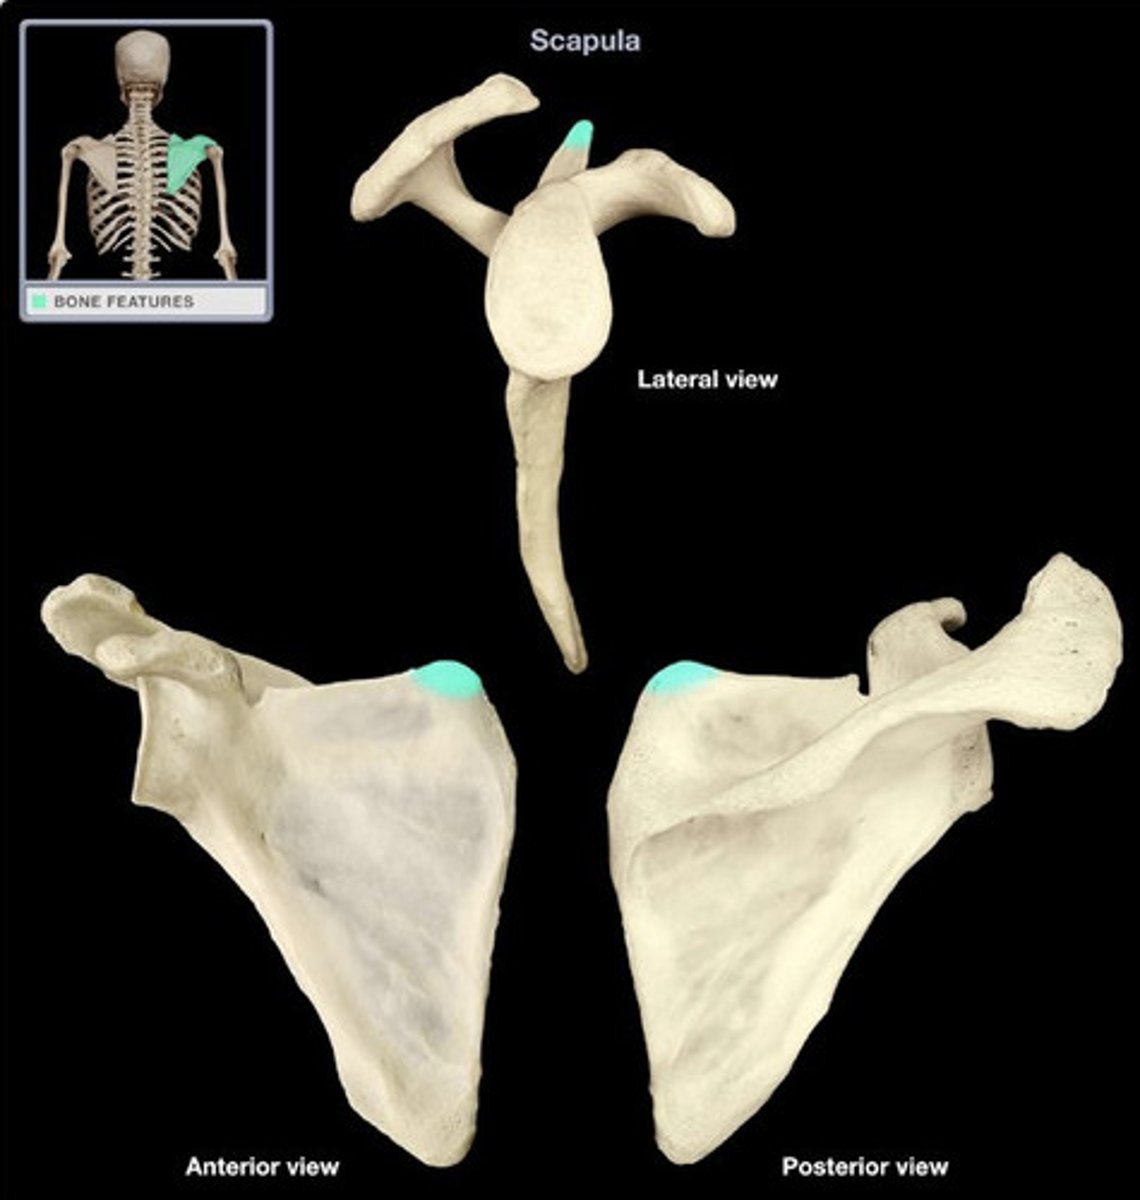

Describe the scapula:

triangular bone

Location of the scapula:

posterior part of the thorax, overlying the 2nd-7th ribs

Scapula articulates with:

humerus (joint) and thoracic wall (physiological scapula-thoracic joint)

Surfaces of the scapula:

- posterior (convex)

- costal (concave)

- lateral

What structures are on the posterior surface of the scapula?

- spine of scapula

- acromion

- supraspinous fossa

- infraspinous fossa

What structure is on the costal surface of the scapula?

subscapular fossa

What structures are on the lateral surface of the scapula?

- glenoid cavity

- coracoid process

- head of scapula

- neck of scapula

- suprascapular notch

Glenoid cavity of the scapula:

- on the lateral surface of the scapula

- located superolaterally receives and articulates with the head of the humerus (glenohumeral joint)

What is the name of the joint between the glenoid cavity and the head of the humerus?

the glenohumeral joint

Coracoid process of scapula:

- on lateral surface of the scapula

- superior to the glenoid cavity, projects anterolaterally